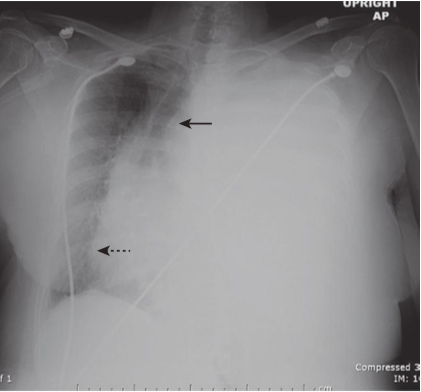

Hydropneumothorax.

hydropneumothorax produces an air-fluid level in the hemithorax marked by a straight edge and a sharp, air-over-fluid interface when the exposure is made with a horizontal x-ray beam (black arrows). This person was stabbed in the right side and there is a moderately large pneumothorax as shown by the visceral pleural white line (white arrows).